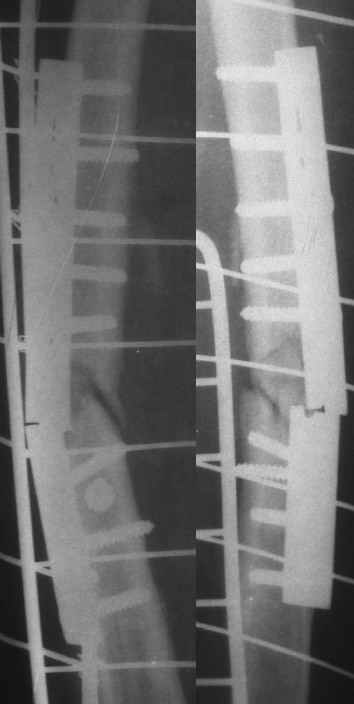

Уважаемые коллеги.Пациентка 18 лет поступила через 6 недель после блокированного остеосинтеза бедра с жалобами на повышение Т до 38гр., незначительной интенсивности боли в Н/3 оперированного бедра, возникающие при движениях (сгибание свыше 90гр.) в коленном суставе. Местно: признаков воспаления, отёка не найдено, пальпация безболезненная. ОАК - N, в моче - капли жира. Картину расценили как проявление жировой эмболии, в течении недели проводилась инфузионная терапия, дезагреганты, постельный режим. Т - N, в моче - жир сохраняется. История болезни этой пациентки началась 5 лет назад с перелома бедра в ДТП, оперирована 2-ы пластиной накостно в одной из больниц нашего города, 2-ы перелом импланта, после последнего раза поступила в нашу клинику, где был выполнен блокированный остеосинтез. Через два года гвоздь удалён (по просьбе больной), Rg-сращение. Через год после удаления рефрактура от незначительной травмы, остеосинтез гвоздём с блок., в раннем послеоперац. периоде жировая эмболия, после купирования амбул. лечение.Прошу советов по дальнейшему лечению. перелом пластины после I опер |  перелом пластины после II опер |  III опер. |  рефрактура через год после удаления штифта |  через мес. после последнего остеосинтеза |